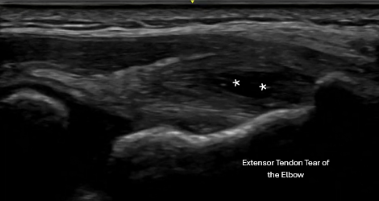

At Physician Coach, every evaluation begins with diagnostic ultrasound performed during your visit and BY THE PHYSICIAN who will be providing the treatment!

We examine your movement and visualize the tissue in real time.

In that same appointment, we determine:

- Exactly which structure is involved

- Whether it’s tendon, joint, or muscle

- The severity of tissue change

- Whether inflammation, degeneration, or partial tearing is present

This is the power of a Physician trained in Diagnostic Ultrasound.